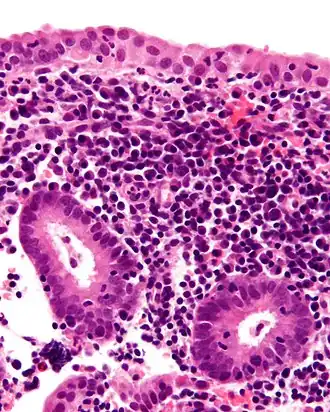

Эндометрит — заболевание, которое вызывается воспалительным процессом в поверхностном слое эндометрия, внутренней слизистой оболочки тела матки[1].

Эндомиометритом называется воспалительный процесс, локализующийся в более глубоких тканях (базальный слой эндометрия, миометрий).